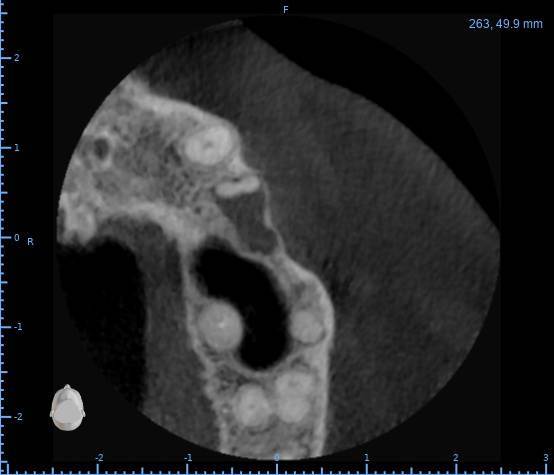

Здравствуйте, появился полгода назад свищ на десне, заполняется и лопается, затягивается и снова появляется, спустя пару месяцев обратился в стоматологию, на снимке ничего критичного не увидели, отправили домой наблюдать тип, еще прошло 3 месяца, так и не проходит и хуже не стало, болей нет никаких, только небольшая если трогать в районе свища, пойдя в другую стоматологию, сделали снимок и так же непонятно что и почему, пошел на КТ, и обратно в стоматологию, есть какая то полость, можно попробовать но нет гарантии, что пройдет, прикрепляю снимок К

ТРезультаты и плюс программа для открытия